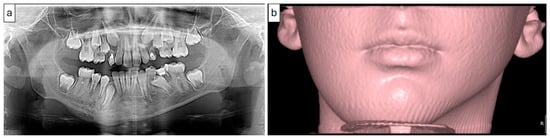

2.1. Case 1

2.1.1. History and Clinical Examination

2.1.2. Radiographic Examination

| 1 | 11 | Left mandible (#32–#37) | Mixed sclerotic and lytic lesion with buccolingual expansion and “onion-skin” periosteal reaction | Irregular bone and fibrous tissue, sclerosis, no inflammation or bacteria | Long-term antibiotic course, NSAIDs | CNO confirmed by imaging, histology, and initial failure to respond to antibiotics | Conservative; antibiotics discontinued after improvement | Improved at 7 months; recurrence at 18 months; no further treatment needed |